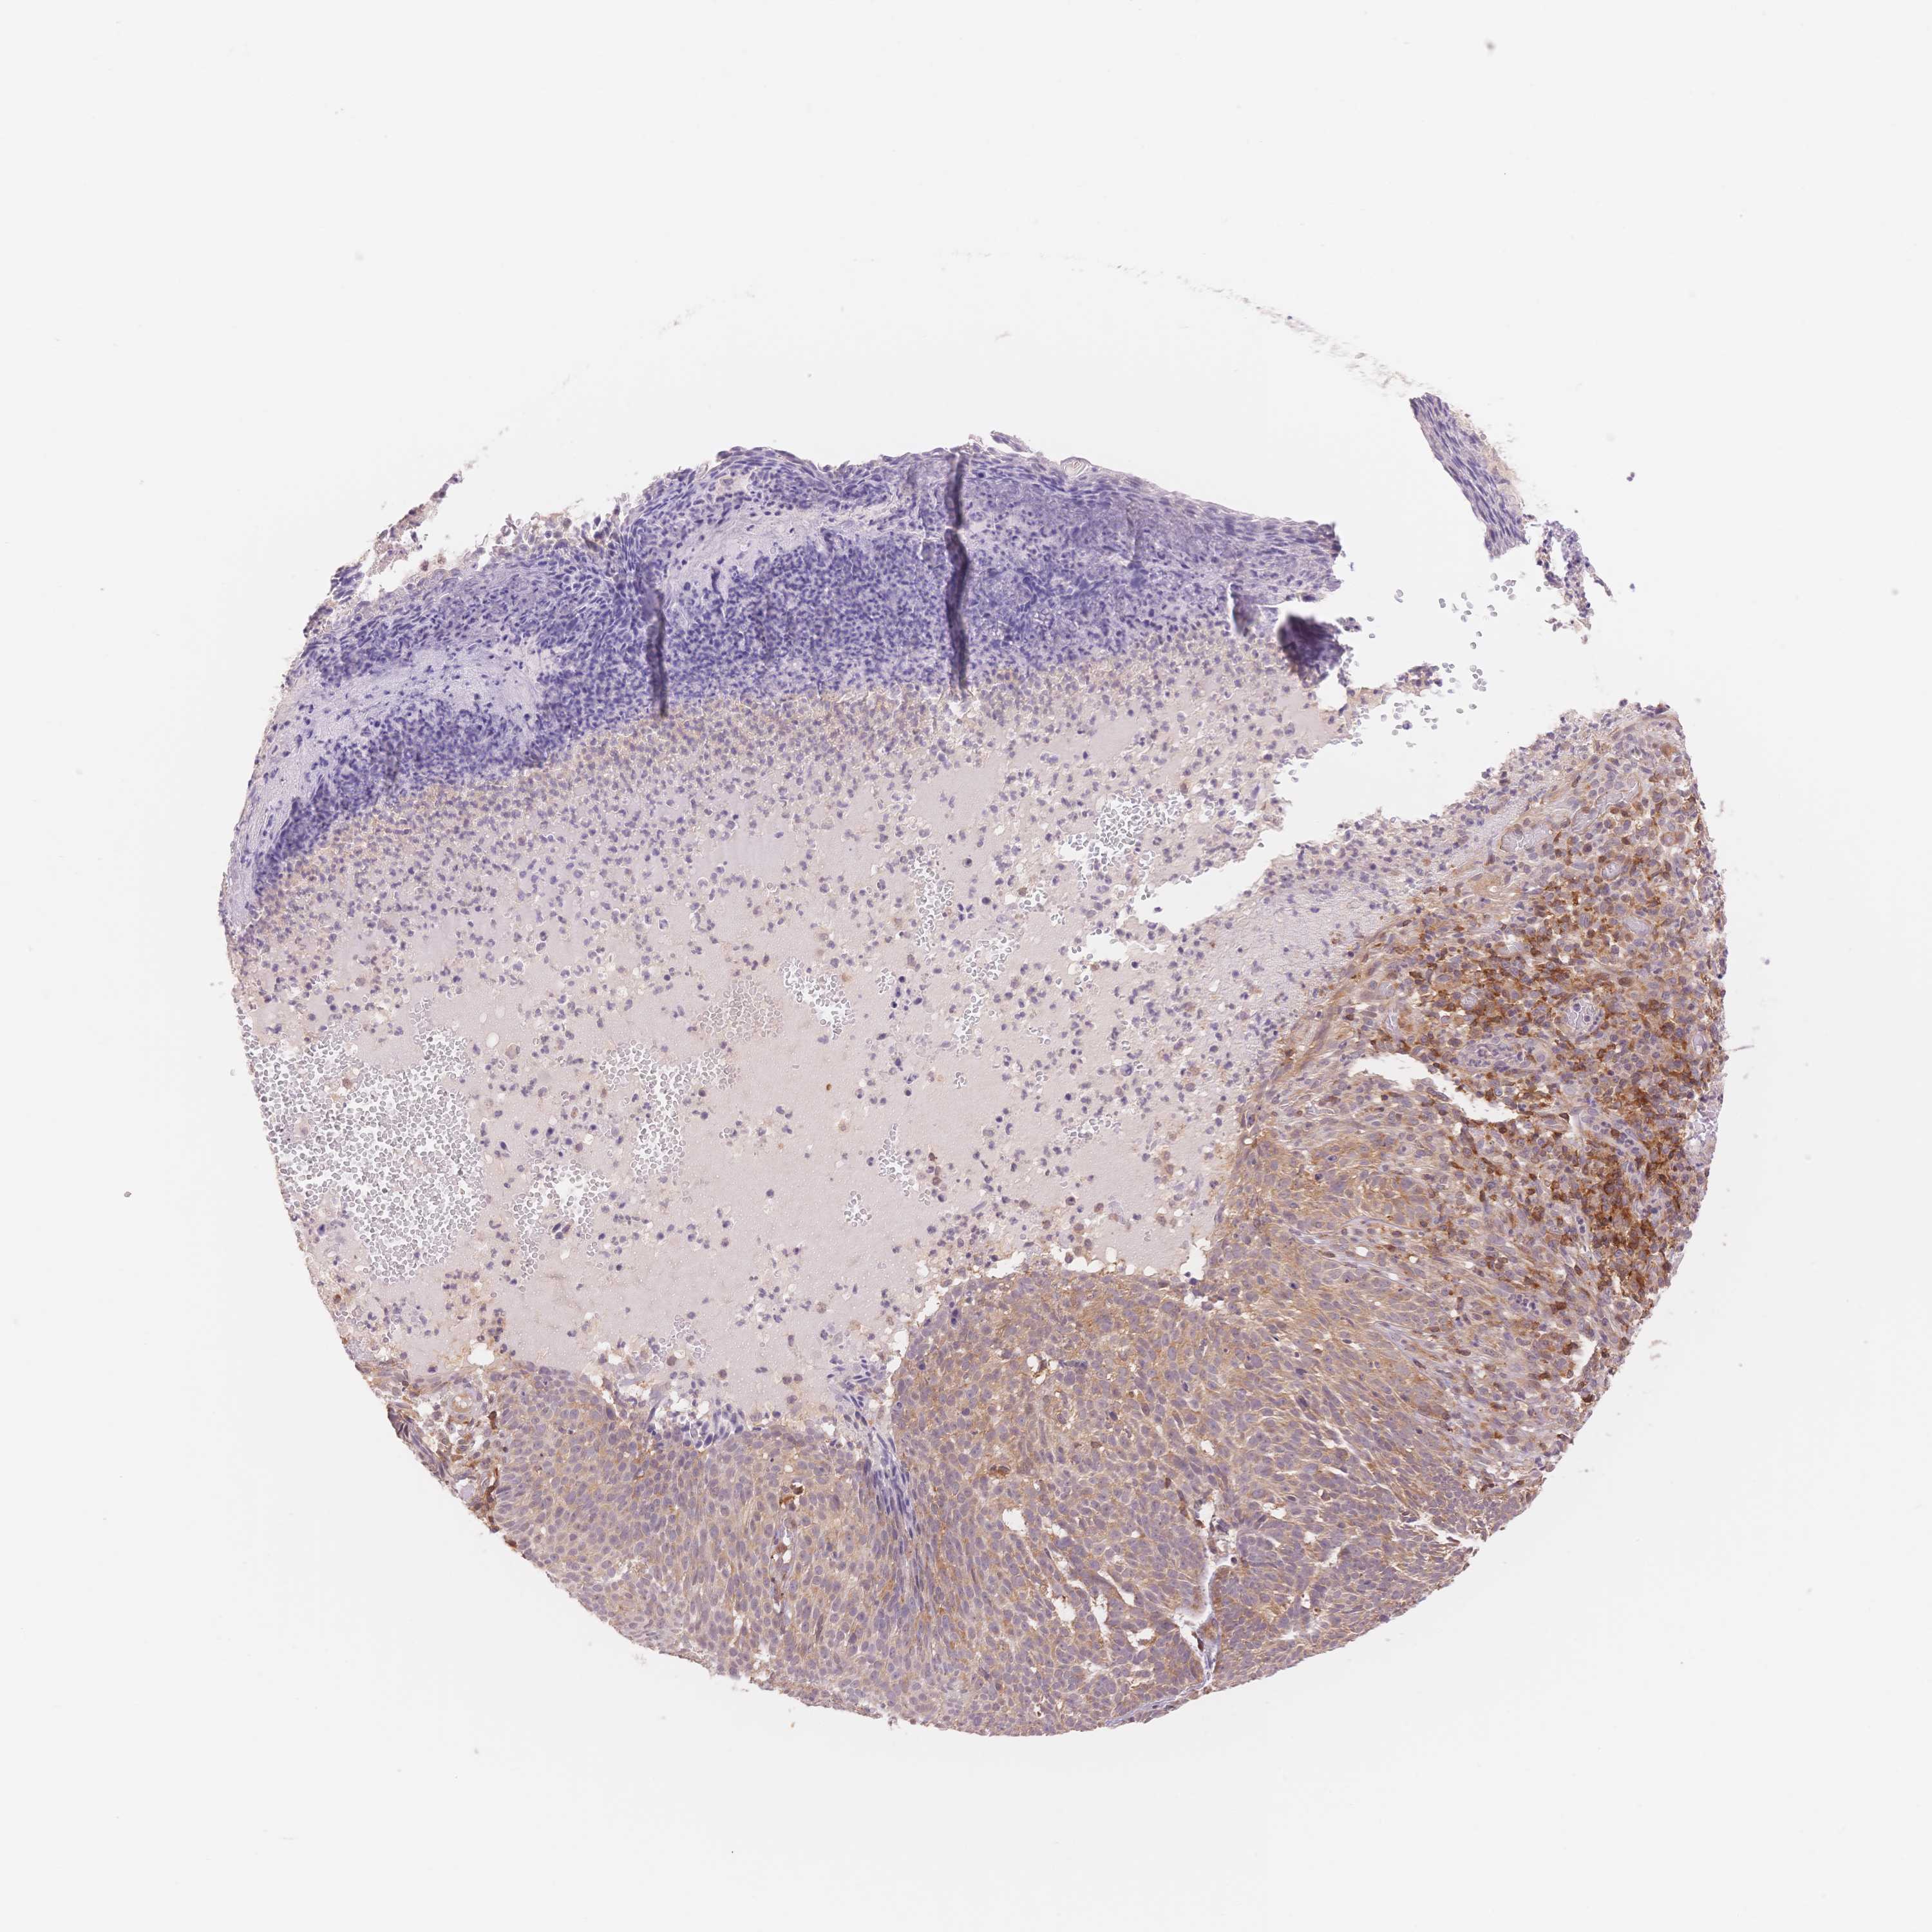

SKIN CANCER - Protein expressioni

A mouse-over function shows sample information and annotation data. Click on an image to view it in a full screen mode. Samples can be filtered based on level of antibody staining by selecting one or several of the following categories: high, medium, low and not detected. The assay and annotation is described here.

Each image is clickable and will lead to virtual microscopy that enables deeper exploration of all samples and also displays staining intensity scores, fraction scores and subcellular localization as well as patient and tissue information for each sample.

Antibody HPA062802

Squamous cell carcinoma, NOS